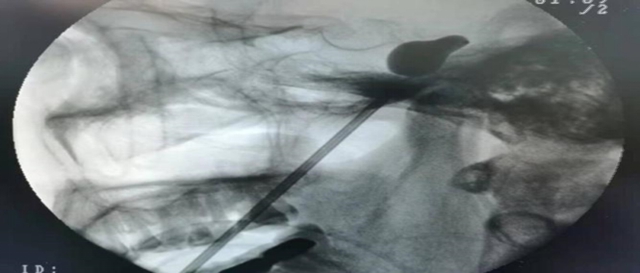

2025年8月10日,羅阿姨到合江縣中醫(yī)醫(yī)院疼痛科就診,疼痛科醫(yī)生以“右側(cè)三叉神經(jīng)痛”收入院,入院時(shí)疼痛數(shù)字評分7分。完善相關(guān)輔助檢查,診斷為原發(fā)性三叉神經(jīng)痛。第二天醫(yī)生為羅阿姨行“右側(cè)經(jīng)皮三叉神經(jīng)半月節(jié)球囊壓迫術(shù)。術(shù)后疼痛數(shù)字評分1分,現(xiàn)已康復(fù)出院。

經(jīng)皮穿刺三叉神經(jīng)微創(chuàng)球囊壓迫術(shù)(pmc):患者在全麻下,經(jīng)c形臂的引導(dǎo),從面部皮膚穿刺達(dá)到三叉神經(jīng)出顱腔的部位——卵圓孔,以球囊導(dǎo)管置入麥克氏囊,通過球囊擴(kuò)張適度壓迫三叉神經(jīng)半月節(jié),充分阻斷三叉神經(jīng)的痛覺神經(jīng)元,達(dá)到治療的目的。